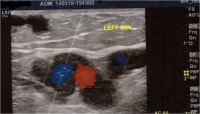

Όπως εξηγεί, η εξέταση με το έγχρωμο Duplex (Triplex), είναι μία εξέταση με υπέρηχους, η οποία είναι τελείως ανώδυνη και απόλυτα ανεκτή για τον ασθενή, αποκαλύπτοντας τόσο το εν τω βάθει όσο και το επιπολής φλεβικό «δέντρο», με ιδιαίτερη λεπτομέρεια, απεικονίζοντας την παρουσία της ροής του αίματος στις φλέβες, αλλά και το σημαντικότερο, την κατεύθυνση αυτής της ροής, προκειμένου να διαγνωσθεί τυχόν παλινδρόμηση.

«Ο απεικονιστικός έλεγχος με υπερήχους σε ασθενείς με κιρσούς είναι απαραίτητος καθώς αποτελεί το κλειδί για την σωστή διάγνωση των κιρσών και καθοδηγεί τον αγγειοχειρουργό στον σχεδιασμό της σωστής θεραπείας που θα προσφέρει άμεση ανακούφιση και άριστο λειτουργικό και αισθητικό αποτέλεσμα που διαρκεί», υπογραμμίζει ο κ. Ματθαίου και συνεχίζει: «Χρειάζεται όμως ο ιατρός να έχει εκπαιδευθεί στη χρήση των υπερήχων και παράλληλα να διαθέτει σημαντική εμπειρία».